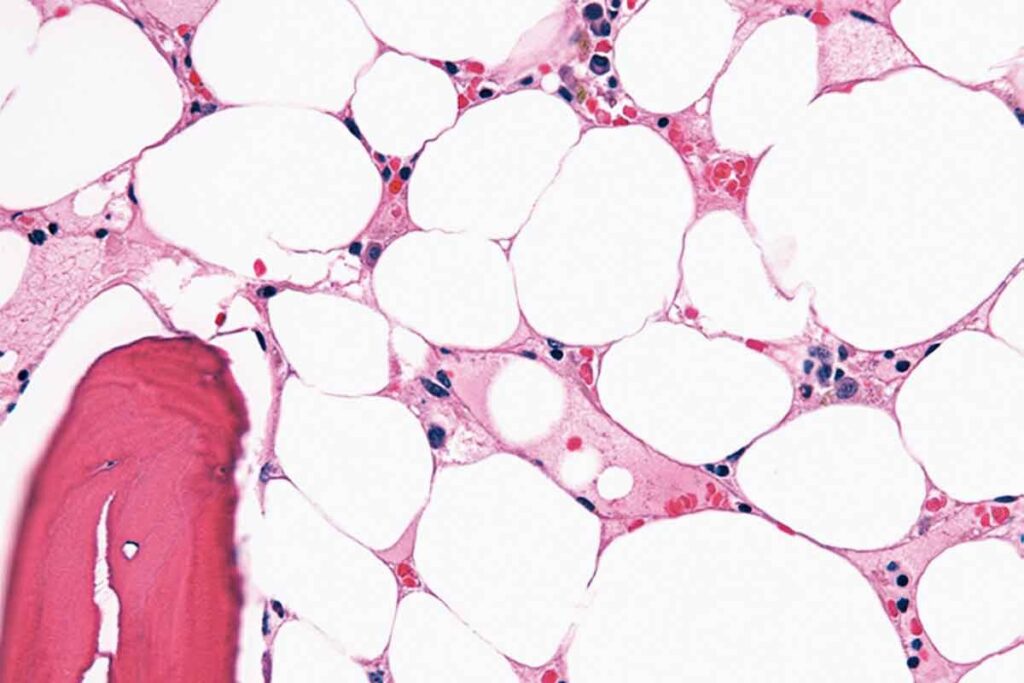

Bone Marrow Failure in Aplastic Anemia

In aplastic anemia, the bone marrow can’t make enough blood cells. This happens when the bone marrow gets damaged. It leads to fewer red blood cells, white blood cells, and platelets.

People with aplastic anemia might feel tired, get infections easily, and bleed a lot. The bone marrow’s failure to make enough blood cells is a key sign of this condition. Knowing how this works helps doctors find better treatments.

Bone Marrow Biopsy and Aspiration

A bone marrow biopsy and aspiration are vital for confirming aplastic anemia. These procedures remove a bone marrow sample for examination. In aplastic anemia, the bone marrow has fewer cells than normal.

The biopsy helps assess the marrow’s health and look for abnormalities like fibrosis or cancer cells.